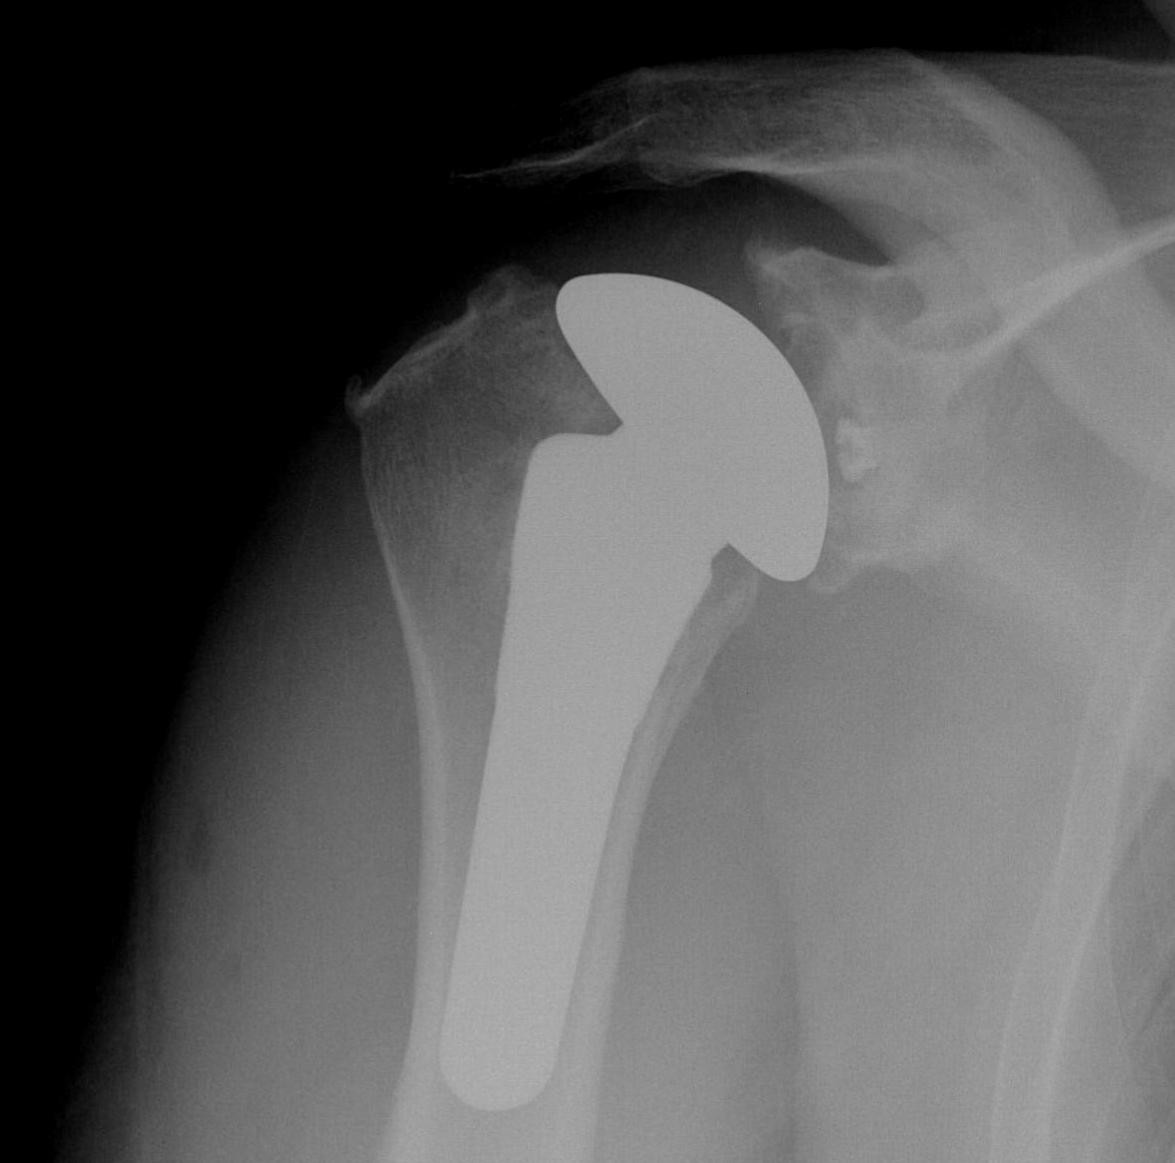

Trial

Should be able to

A. Inferiorly sublux head 50% glenoid and return to center

B. Posteriorly sublux head 50% and return to center

C. Able to close subscapularis without impingement on head